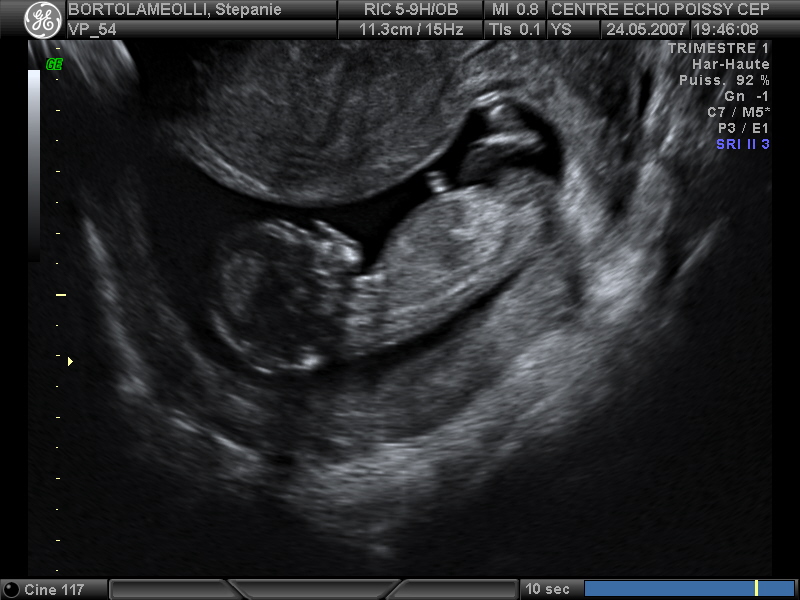

Echographies

Mai 2007